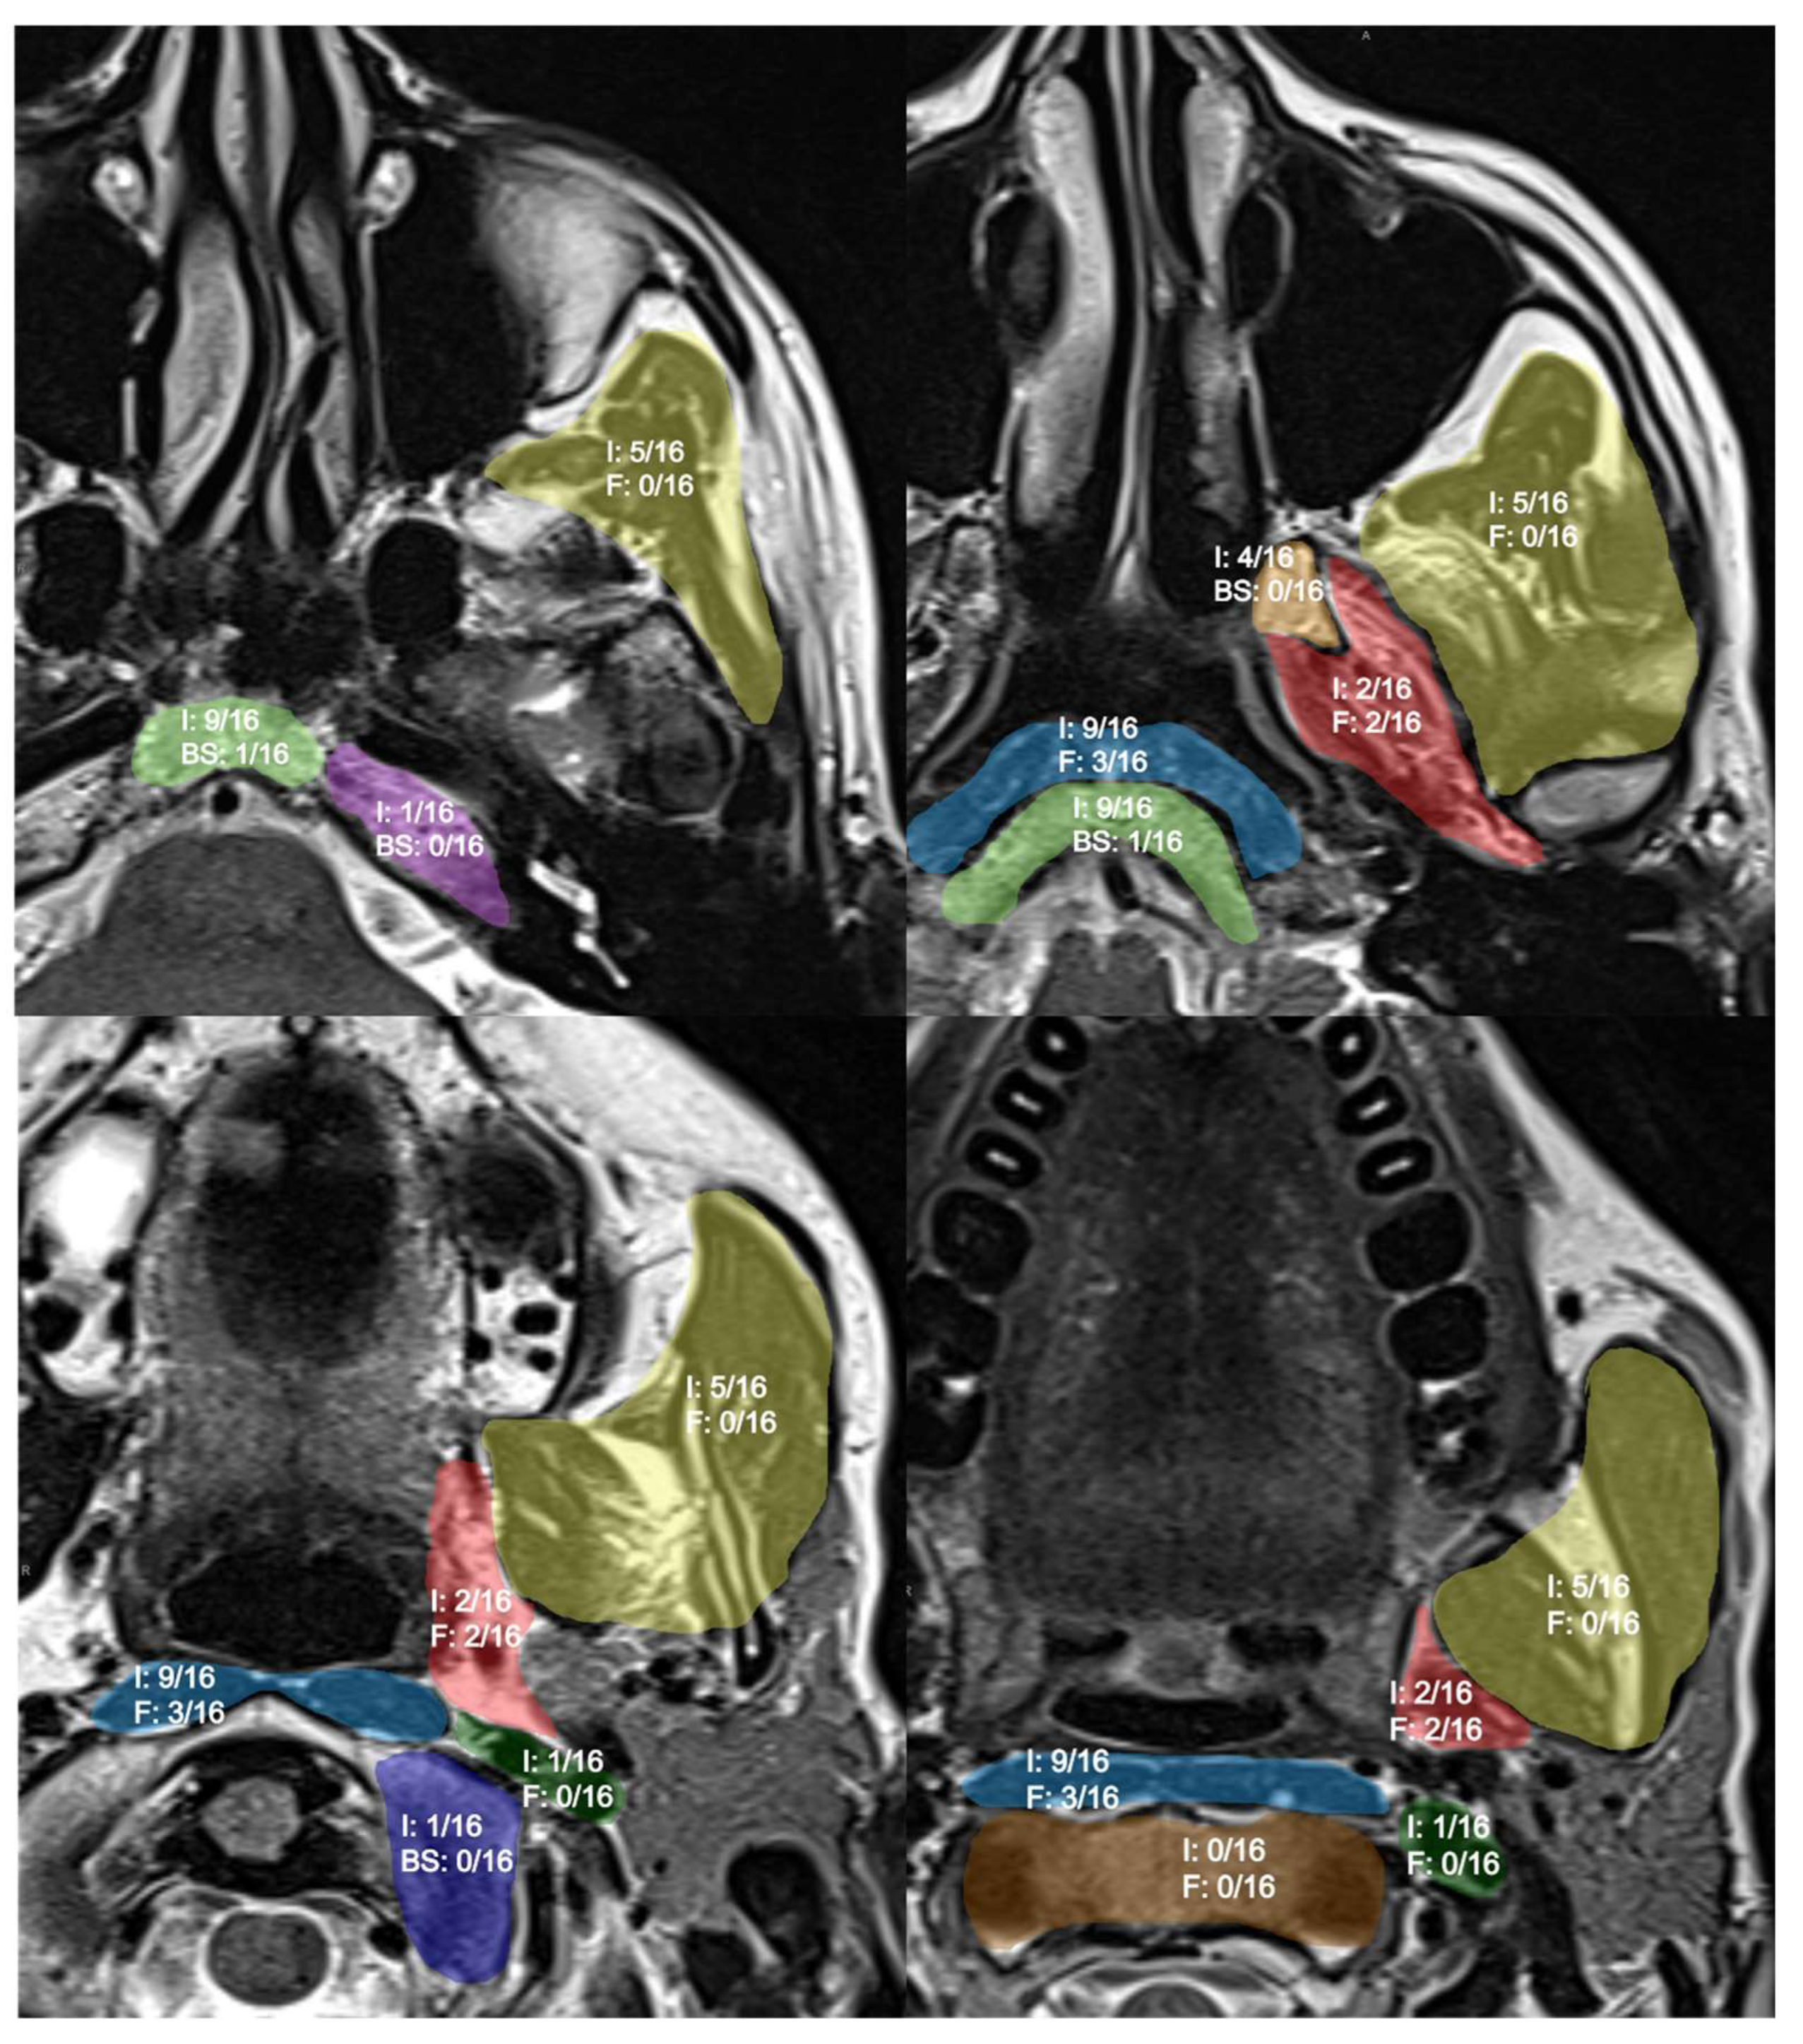

3.2. Imaging Findings—Anatomical Spaces

| Anatomical Subsite | Inflammation | Fibrosis | ||||

|---|---|---|---|---|---|---|

| First MRI | Second MRI | Variation | First MRI | Second MRI | Variation | |

| Parapharyngeal space | 2 | 1 | ↓1 | 2 | 2 | = |

| Retropharyngeal space | 9 | 4 | ↓5 | 3 | 3 | = |

| Masticator space | 5 | 2 | ↓3 | 0 | 0 | = |

| Carotid space | 1 | 0 | ↓1 | 0 | 0 | = |